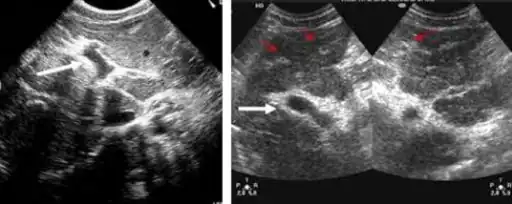

Ultrasonographic images in hepatic schistosomiasis